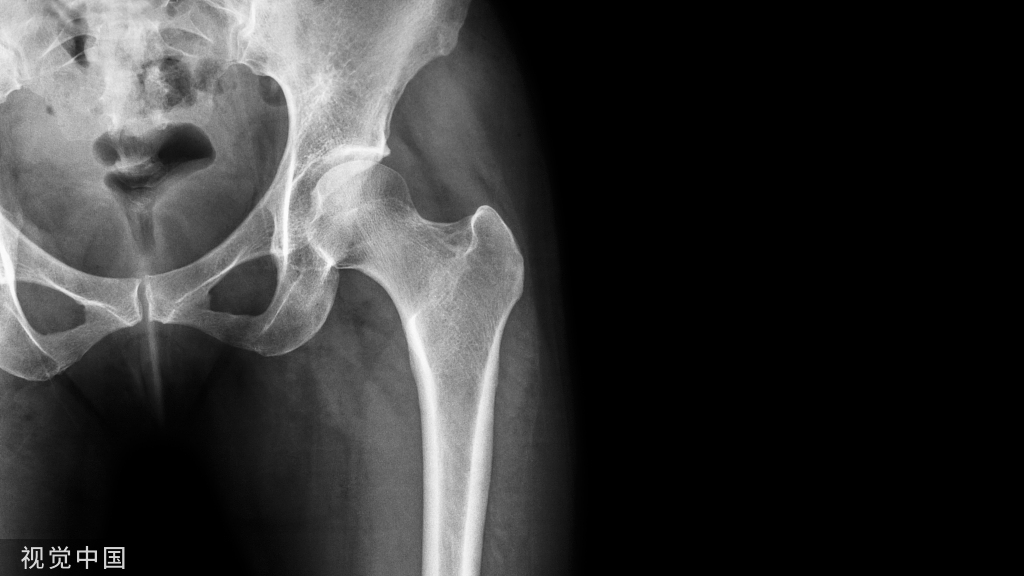

骺板的血液供应②Dale和Harris将骺板的血供分成2型:A.骨骺几乎完全被关节软骨覆盖,如股骨和桡骨近端,血管穿过软骨膜后仅能供应骨骺的外周。B.仅部分关节软骨覆盖的骨骺,骺板的血供来自骨骺。

骺板的血液供应③一但发生骨骺在干骺端的分离损伤:A型   骺生长板血供易受累。(股骨头缺血坏死,桡骨头缺血坏死)B型   骺生长板血供受影响少。